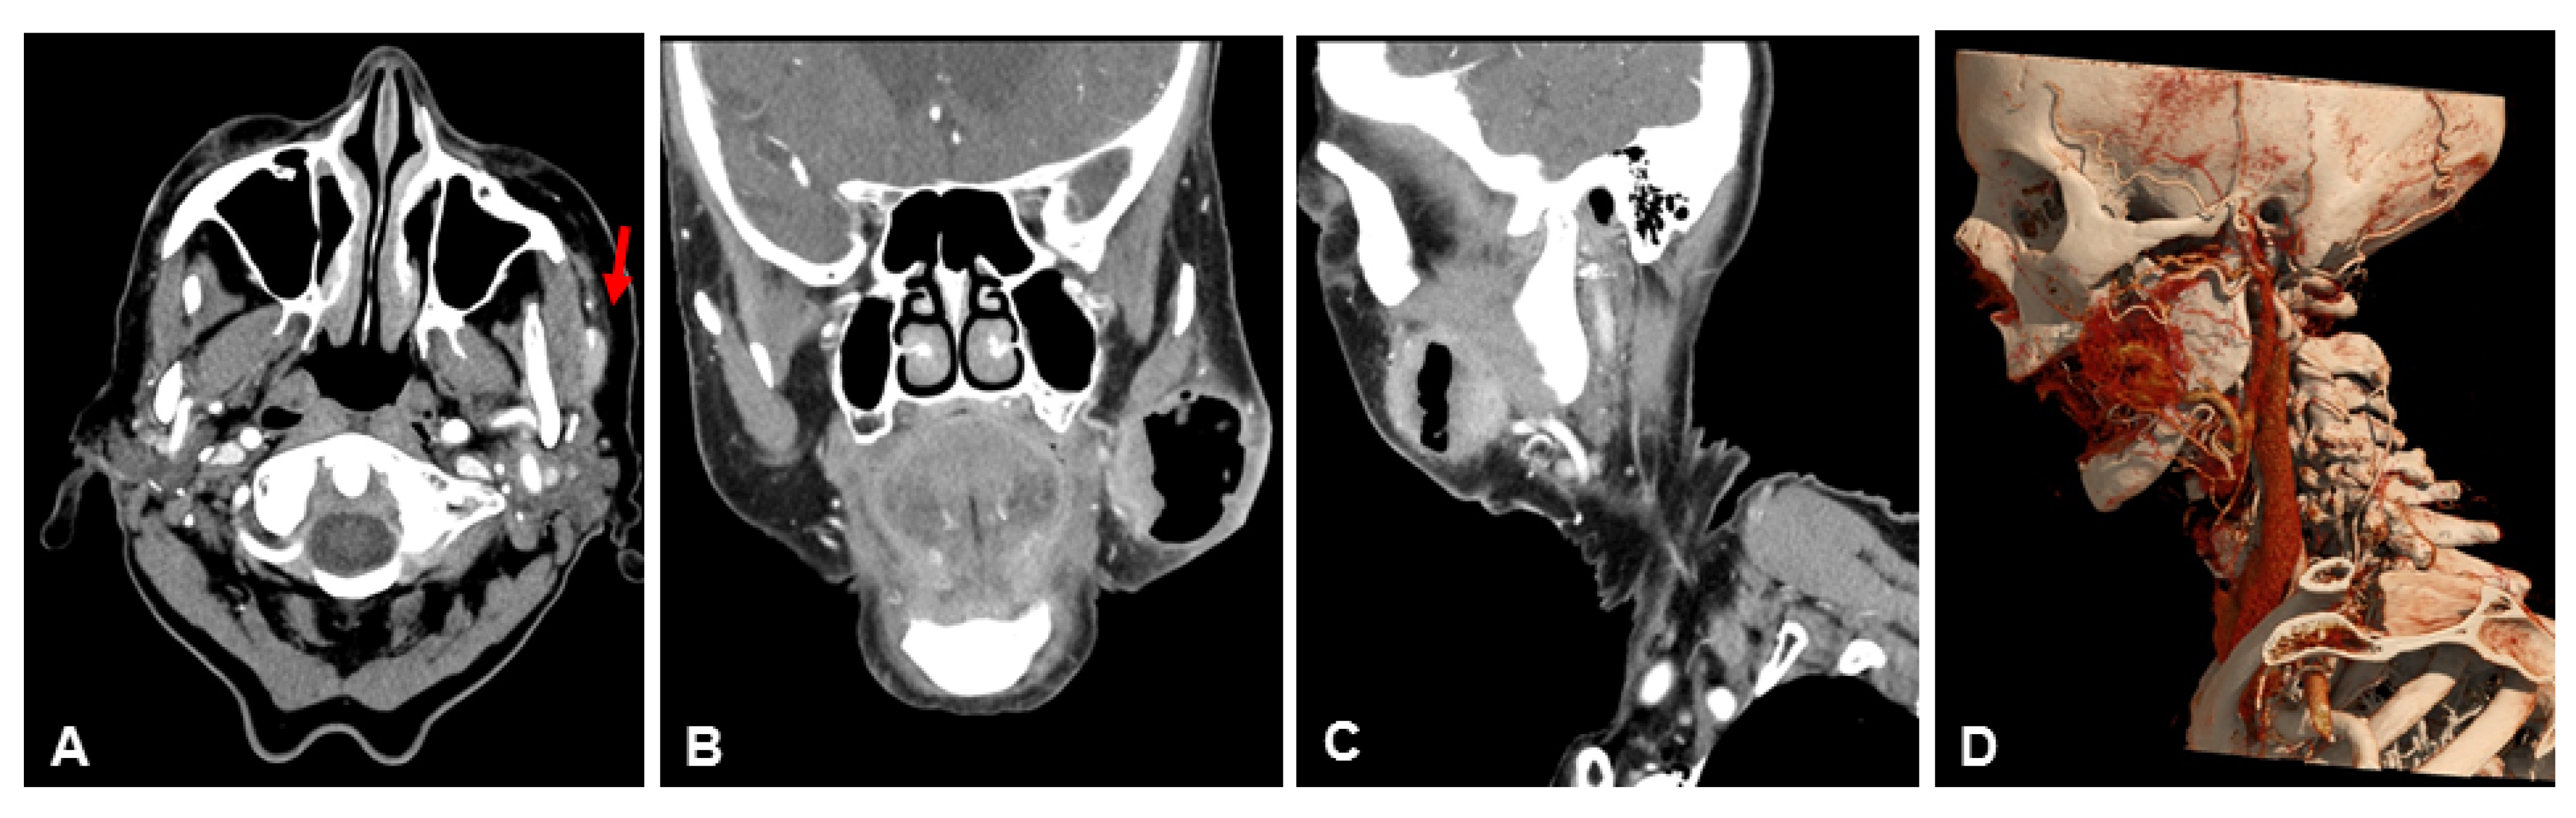

Table 3 lists the scores of both readers for subjective image quality in detail. Patient examples are given in Figure 4, Figure 5 and Figure 6.

Figure 5. Example of a 57-year-old male patient with a squamous cell carcinoma of the lateral border of the tongue. Patient underwent initial resection. Both NR-CT and UHR-CT were performed after resection, and the carcinoma shows no signs of recurrence. Note the remarkably improved delineation of muscle and vessels with UHR-CT. (A) axial 3 mm reconstruction NR-CT, (B) coronal 3 mm reconstruction NR-CT, (C) sagittal 3 mm reconstruction NR-CT, (D) best possible 3D-reconstruction NR-CT, (E) axial 3 mm reconstruction UHR-CT, (F) coronal 3 mm reconstruction UHR-CT, (G) sagittal 3 mm reconstruction UHR-CT, (H) best possible 3D-reconstruction UHR-CT.